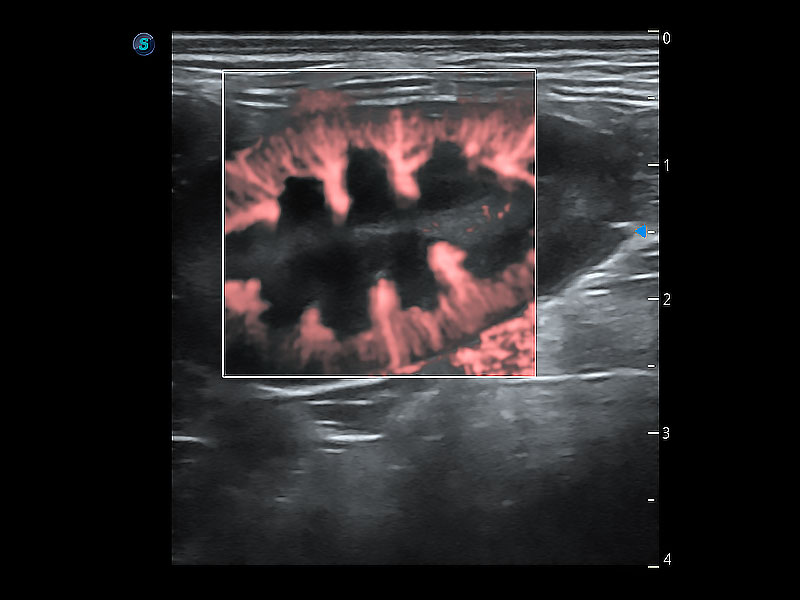

在傳統(tǒng)二維血流成像的基礎(chǔ)上,呈現(xiàn)血流的立體感,具有動(dòng)感的生命力之美。即便是微小的血管也能輕松應(yīng)對(duì),提高了血流的視覺敏感性。